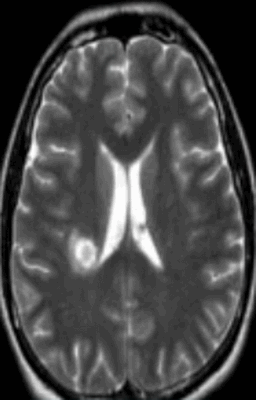

- Стадия 1 (острая): До 4 нед. после повреждения на традиционных МР-изображениях не определяются патологические изменения сигнала.

- Стадия 2 (подострая): Спустя 4-14 нед. на Т2-ВИ визуализируется гипоинтенсивная зона, обусловленная начальным, а не биохимическим распадом миелина и компонентов аксона.

- Стадия 3 (хроническая): Гиперинтенсивная зона на Т2-ВИ (распад жиров и липопротеинов, вазогенный отек, глиоз).

- Стадия 4: Атрофия

- Раннее выявление возможно при использовании метода переноса намагниченности (ПМ) и диффузионно-взвешенных изображений.

Валлеровская дегенерация вследствие инсульта в бассейне средней мозговой артерии в левом полушарии большого мозга. Р1_А1К-изображения (а, b) и Т2-ВИ в аксиальной плоскости (с). В зоне, кровоснабжаемой левой средней мозговой артерией, визуализируется кистозный дефект с глиозом (а). Определяется повышенная интенсивность сигнала от пирамидного пути в левой ножке мозга (b) и в продолговатом мозге слева (с).